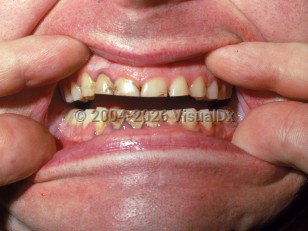

Lead poisoningLead poisoning

Arsenic poisoningArsenic poisoning